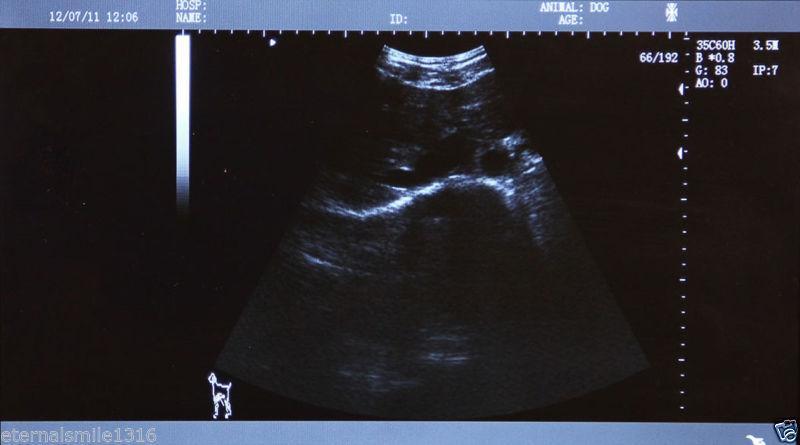

Veterinary vet Digital Laptop Ultrasound Scanner w Rectal Linear Probe 3D A+ 190891459831

Sale price$ 1,955.69

Regular price$ 2,384.99